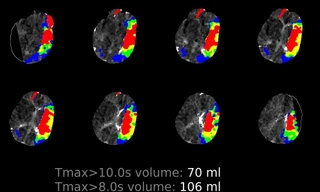

TPO - Phần mềm trí tuệ nhân tạo Rapid được ứng dụng tại Bệnh viện Nhân Dân 115 đã cứu sống hơn 1.000 bệnh nhân đột quỵ nhập viện khi đã quá “giờ vàng”. Đây là một trong những thành công nổi bật trong phát triển Đề án Y tế thông minh trên địa bàn TPHCM.